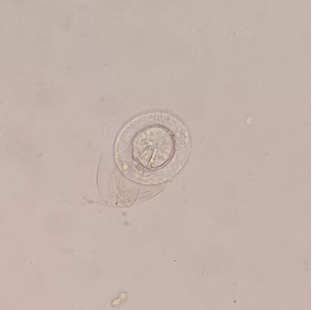

Ovo de Hymenolepsis nana